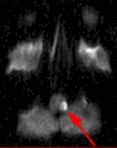

MRI Findings: In the supratentorial regions, some atrophy and chronic small vessel deep white matter ischemic changes were observed (Fig. 1) but no acute lesion or infarct was observed on MR diffusion. In the posterior fossa, however, a subtle small 1 cm hyperintensity can be seen in the left side of medulla on T2 weighted (Fig. 2) and FLAIR images (Fig. 3). This can be seen with an infarct, but its age would remain indeterminate. The MR diffusion image (Fig. 4) shows hyperintensity in the same region consistent with an acute infarct (arrows) as opposed to chronic ischemic changes.

Final Diagnosis: Based on the MR appearance, diagnosis of acute lateral medullary infarct was provided. This is a classic appearance of a posterior inferior cerebellar artery (PICA) infarct (PICA Syndrome), which may have thrombosed.